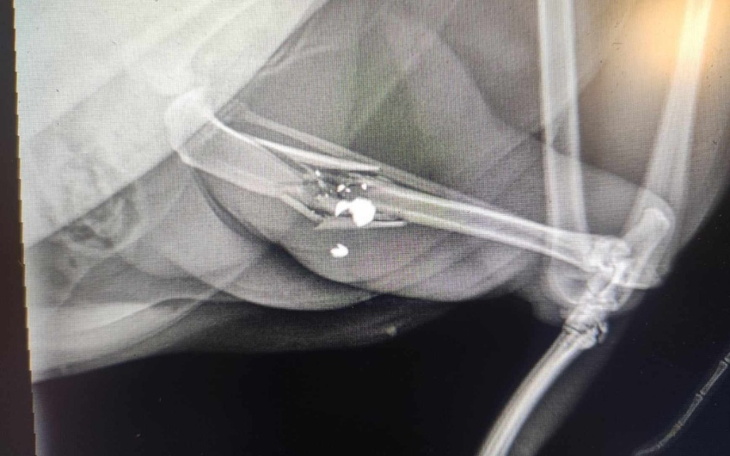

Witam zbieram pieniądze na pokrycie kosztów zabiegu operacyjnego mojej kotki postrzelonej ze śrutówki. Kotka ma strzaskaną tylnią łapkę, bardzo cierpi. Musi mieć usunięty śrut, ponieważ grozi jej śmierć w męczarniach. Oczywiście sprawa jest zgłoszona na policję, ale my nie możemy czekać do zakończenia postępowania. Bardzo proszę o pomoc w uzbieraniu kwoty za operację, która odbędzie się już jutro.